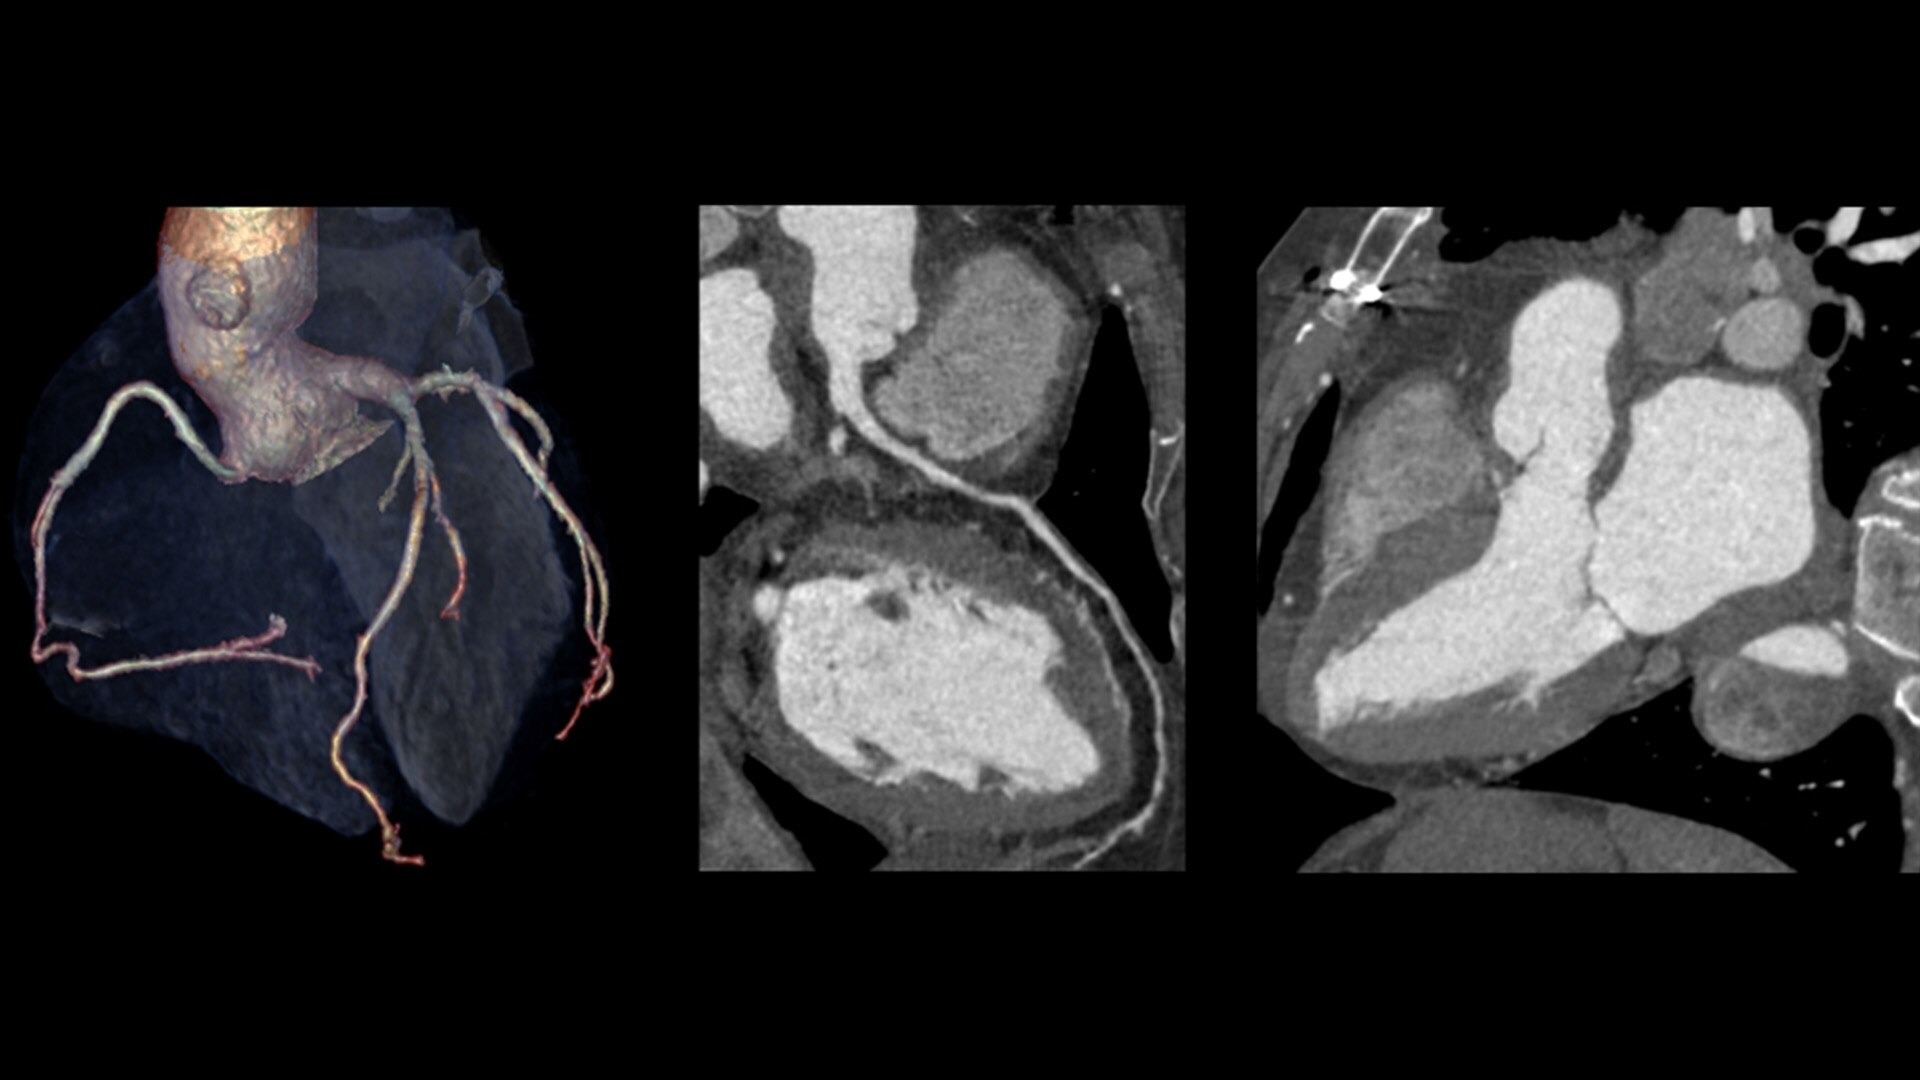

Visualize the whole heart in a single rotation

The 160 mm Clarity Detector's z-coverage makes whole-heart coverage in a single axial rotation a reality. This hardware breakthrough provides outstanding image quality for all patients.